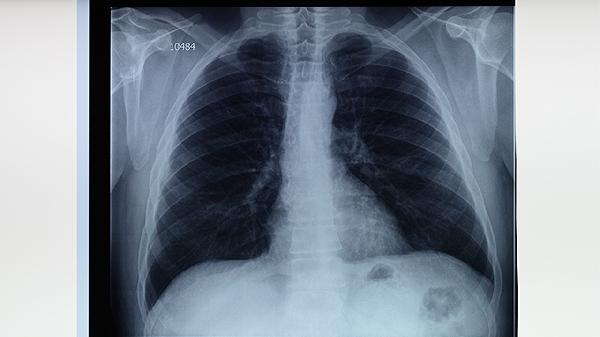

影像学显示纤维条索影或钙化灶可定期随访。若存在厚壁空洞等未闭合病灶,需延长治疗1-3个月。这种情况可能与局部血供差导致药物浓度不足有关,可能继发支气管扩张等并发症。